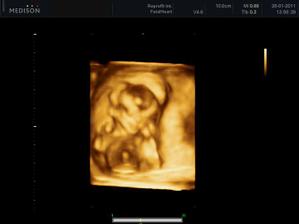

25.3.2011 - 3D utz - tak konečně víme, kdo nám to bydlí v bříšku - je to neuvěřitelný, ale je to malá princezna, hurááá hurááá je to holka - jsme moc šťastní - je to celej táta - i slza ukápla a tátovi taky.A kočenka s panem doktorem opět nespolupracovala, takže maminka opět chodila po chodbě jak trdlo, nakonec se umoudřila a přelehla si na druhej bok, nakonec se nám postavila na hlavu, asi jako už mě nechte být, no byla to sranda - krásný zážitek a nakupujeme růžovou 🙂 - měříme 24 cm a vážíme 320 g